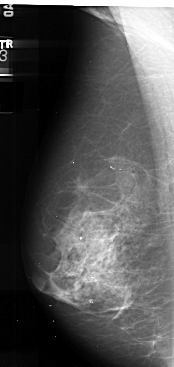

A_1035_1.LEFT_MLO

LEFT_MLO LINES 5491 PIXELS_PER_LINE 2596 BITS_PER_PIXEL 16 RESOLUTION 42 NON_OVERLAY